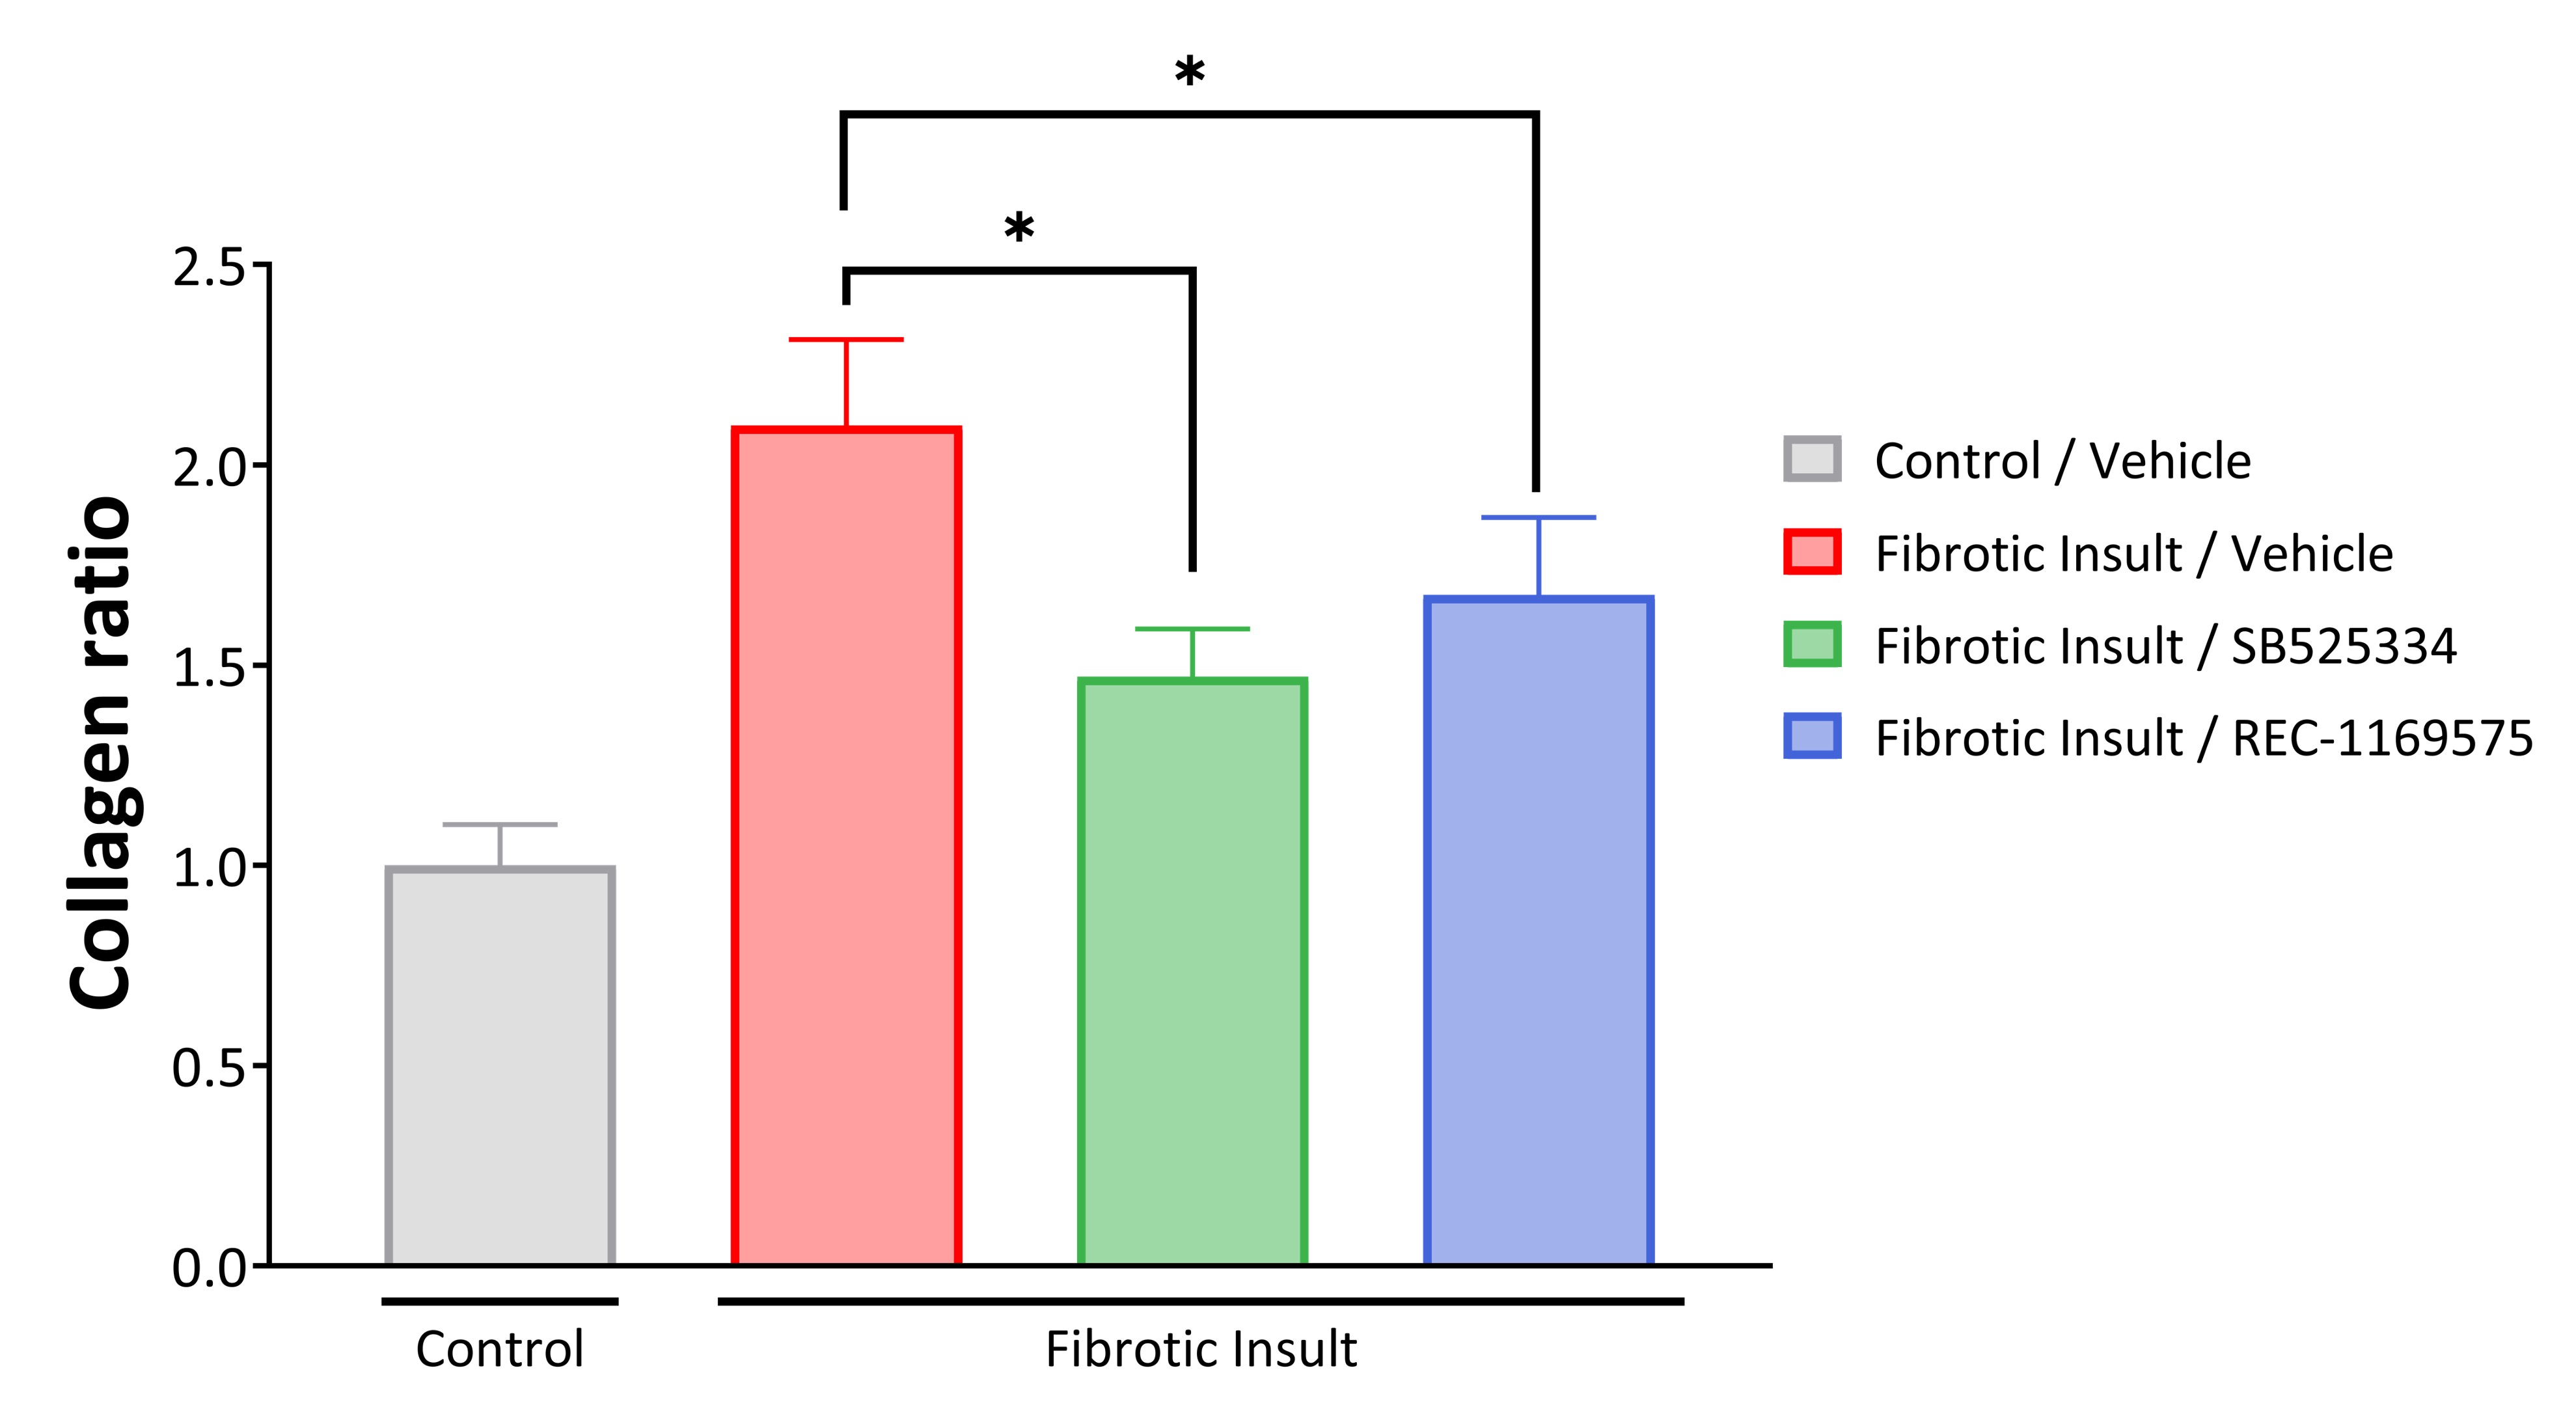

•In-licensed a program (Target Epsilon) that emerged from our fibrosis collaboration with Bayer that represents a novel approach to treating fibrotic diseases with compelling early data